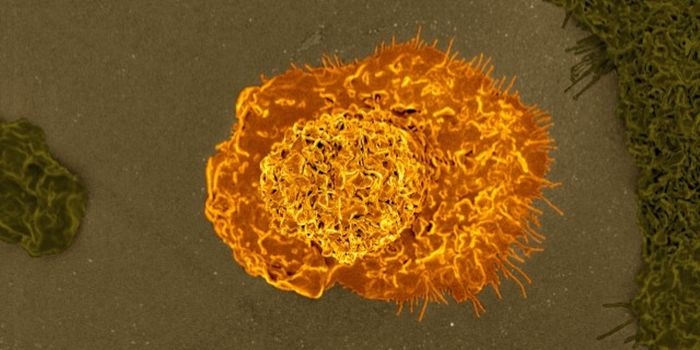

JAN 28, 2021ImmunologyNatural killer cells, or NK cells, are specialized immune cells of the innate immune system. Their job revolves around e ...